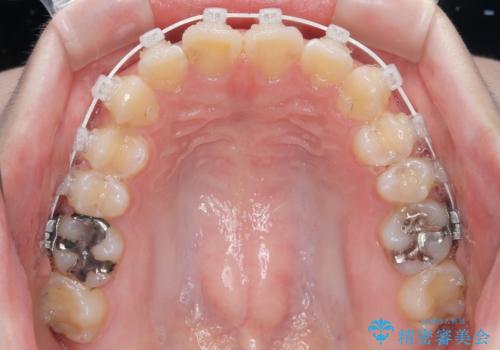

- 矯正装置

- 審美装置

- 上下前歯部のデコボコを気にして来院された患者様です。

叢生は軽度であったため、マウスピースでもワイヤー装置でも対応可能でしたが、マウスピースを長時間使用する自信がないとのことでワイヤー装置にて矯正治療を行うこととしました。

叢生が軽度であったため、僅か半年で装置を除去することができました。